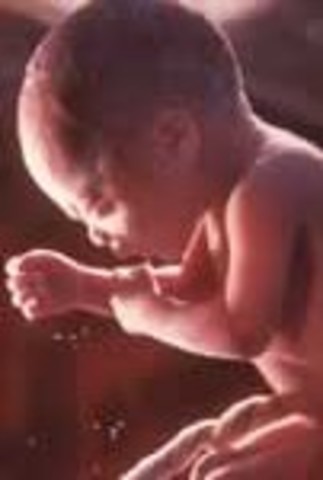

• Week 27

Week 27

This is the start of the third trimester and the look of the baby will be the same at birth. The brain is rapidly growing, and the retina of the eyes are developing.